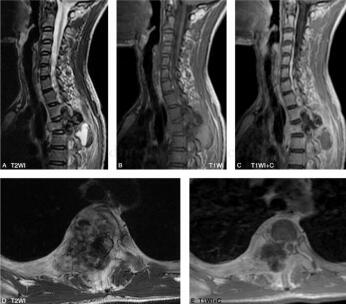

图2 MR:胸2椎体及附件骨质破坏,椎体变扁,呈菜花状改变,相应椎管内呈不规则稍长T1、短T2信号,棘突旁见囊状长T1长T2信号,后方见短T2信号,两者间见液液平面。增强扫描边缘强化